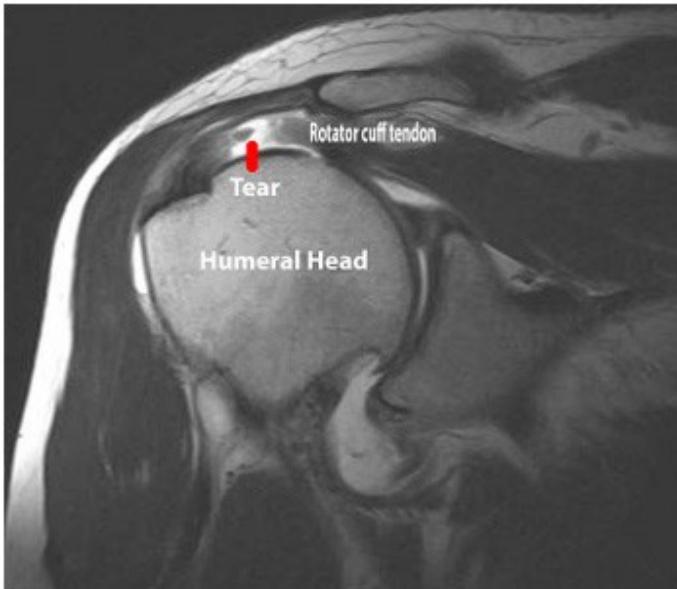

Section 3: Shoulder Pathology & Examination

Questions 17-20: Shoulder Injuries and Tests

Clinical Scenario: 45 years old male fell from height and landed on his shoulder and presented to your clinic with painful shoulder.

Q17: What is the following test name and what does it test?

Apprehension test for anterior shoulder instability

Q18: What is the following test name and what does it test?

Empty can test for Supraspinatus power